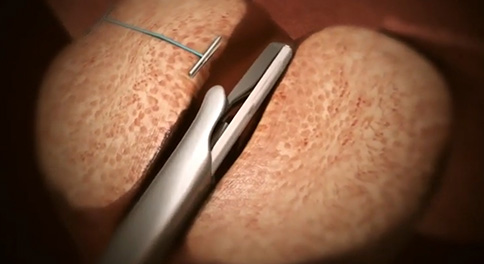

이지용 원장 남성수술 건수

5,000 건 이상

이지용 원장님이 끊임 없이 연구한 성과를 바탕으로

5천례 이상을 집도하며 결과를 입증하고 있습니다.